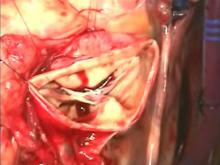

A step-by-step guide for performing an aortic root replacement with the Freestyle Aortic Root. Safeguards and pitfalls are reviewed.